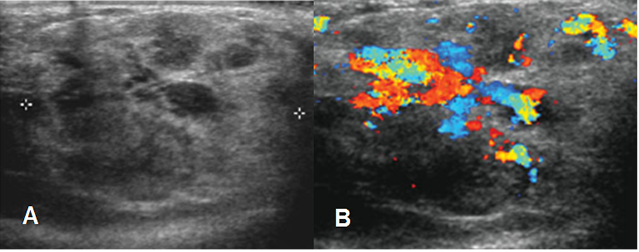

Fig 149. Hemangioma.

A: Ecografía. Imagen heterogénea de bordes parcialmente definidos.

B: Ecografía doppler: Lesión muy vascularizada y con vasos dilatados, que corresponde a hemangioma.